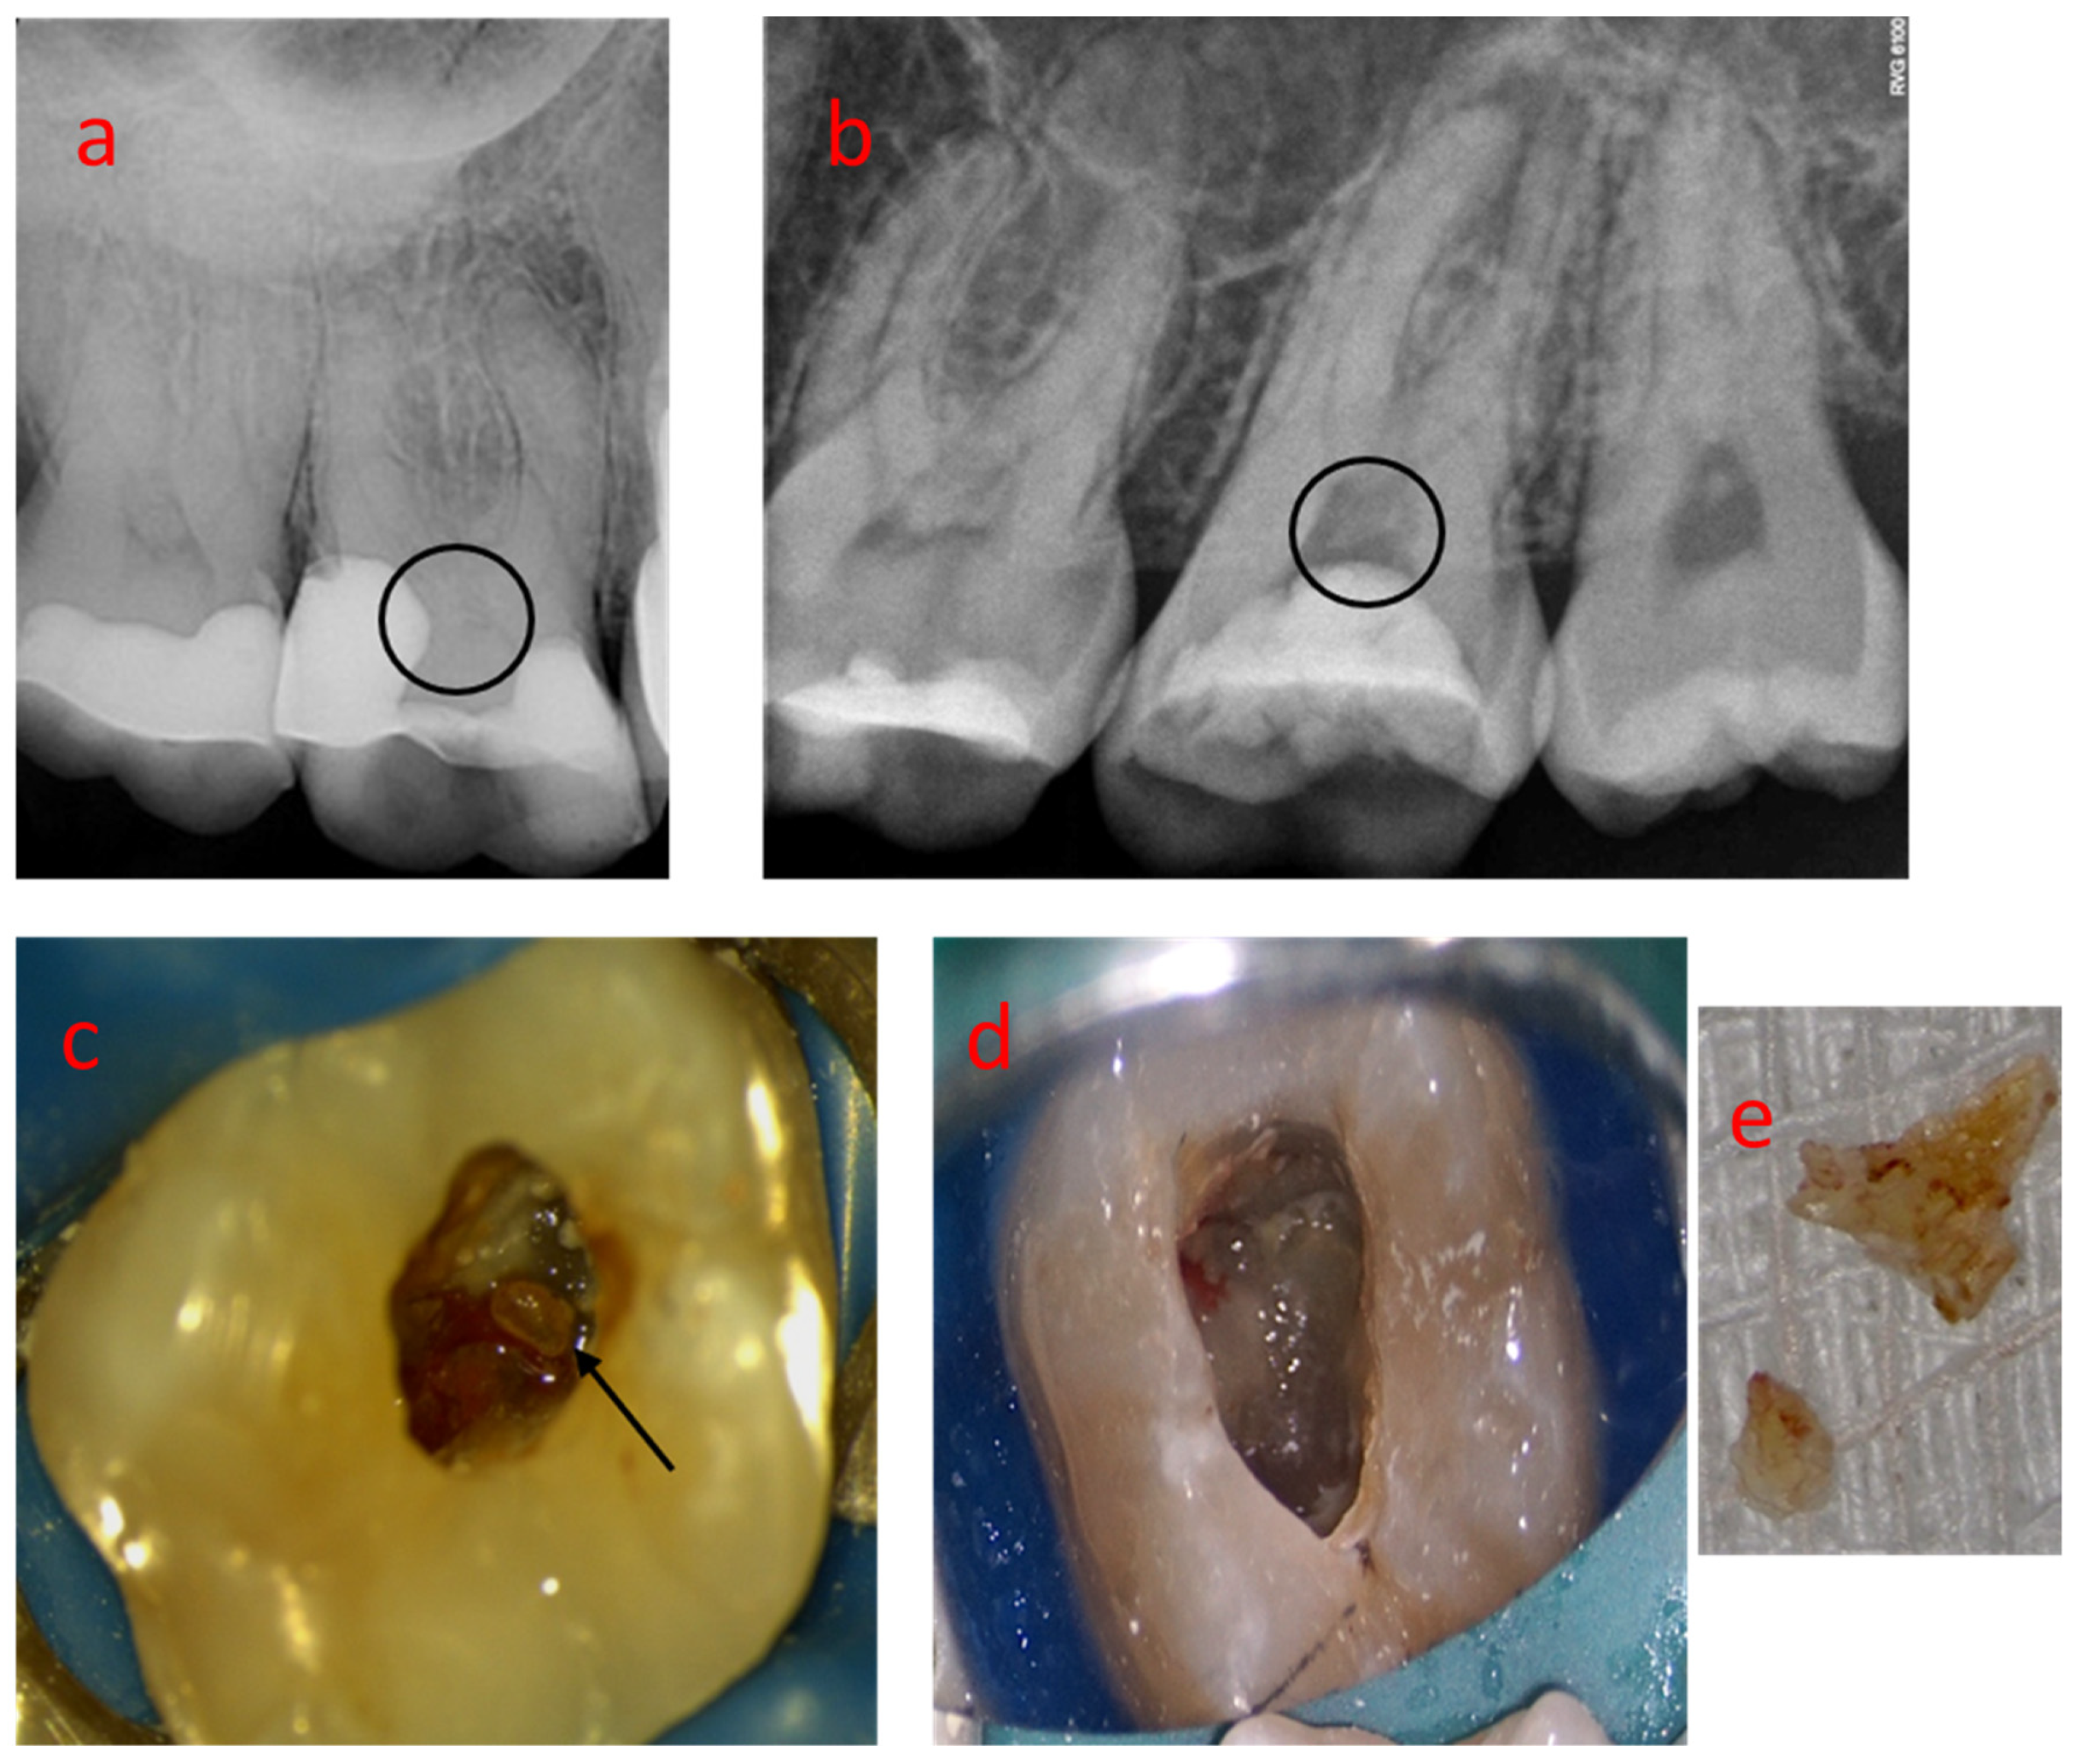

3.5. Sample 05

3.6. Sample 06